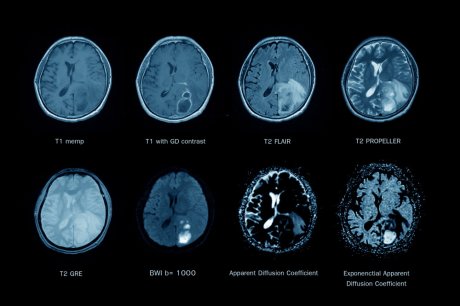

Otkrivanje abnormalnosti uz pomoć magnetne rezonance

Istraživači su, takođe, koristili snimke magnetne rezonance za otkrivanje bilo kakvih abnormalnosti u moždanom tkivu. Analizirano je i područje mozga koje obuhvata čulo mirisa, jer je poznato da je gubitak mirisa jedan od prvih simptoma covid 19. Još jedna regija mozga koju su ispitivali bila je moždano stablo, zadnji deo mozga koji ga povezuje sa kičmenom moždinom, inače presudno za život ljudi, a koje reguliše navike spavanja i ishrane i kontroliše rad srca i brzinu disanja. Da bi procenili relevantna moždana tkiva, istraživači su koristili metod bojenja imunohistohemija, koji omogućava vizualizaciju proteina u ćelijama i tkivima.

mozak ct snimak mri Za detaljnu analizu korišćeni su snimci magnetne rezonance Foto: Shutterstock

Od 19 uzoraka moždanog tkiva, 13 je snimljeno i 10 je pokazalo moždane anomalije. Dalja analiza pokazala je oštećenje krvnih sudova. Kod 9 pacijenata prisustvo lezija ukazivalo je da je reč o povredi i curenju moždanih sudova. Takođe je bilo znakova da u mozgu curi protein krvi koji se zove fibrinogen. Autori studije naglašavaju da je ovo dokaz upale koja nastaje prekomernim delovanjem imunološkog sistema u borbi protiv infekcije. Kod 10 pacijenata, snimci magnetne rezonance pokazale su hipointenzitet koji odgovara zagušenim krvnim sudovima i akumulaciju fibrinogena oko tog područja. Naučnici su naveli da ovi rezultati istraživanja ukazuju da bi ovaj proces mogao da bude uzrokovan upalnim odgovorom tela na virus.